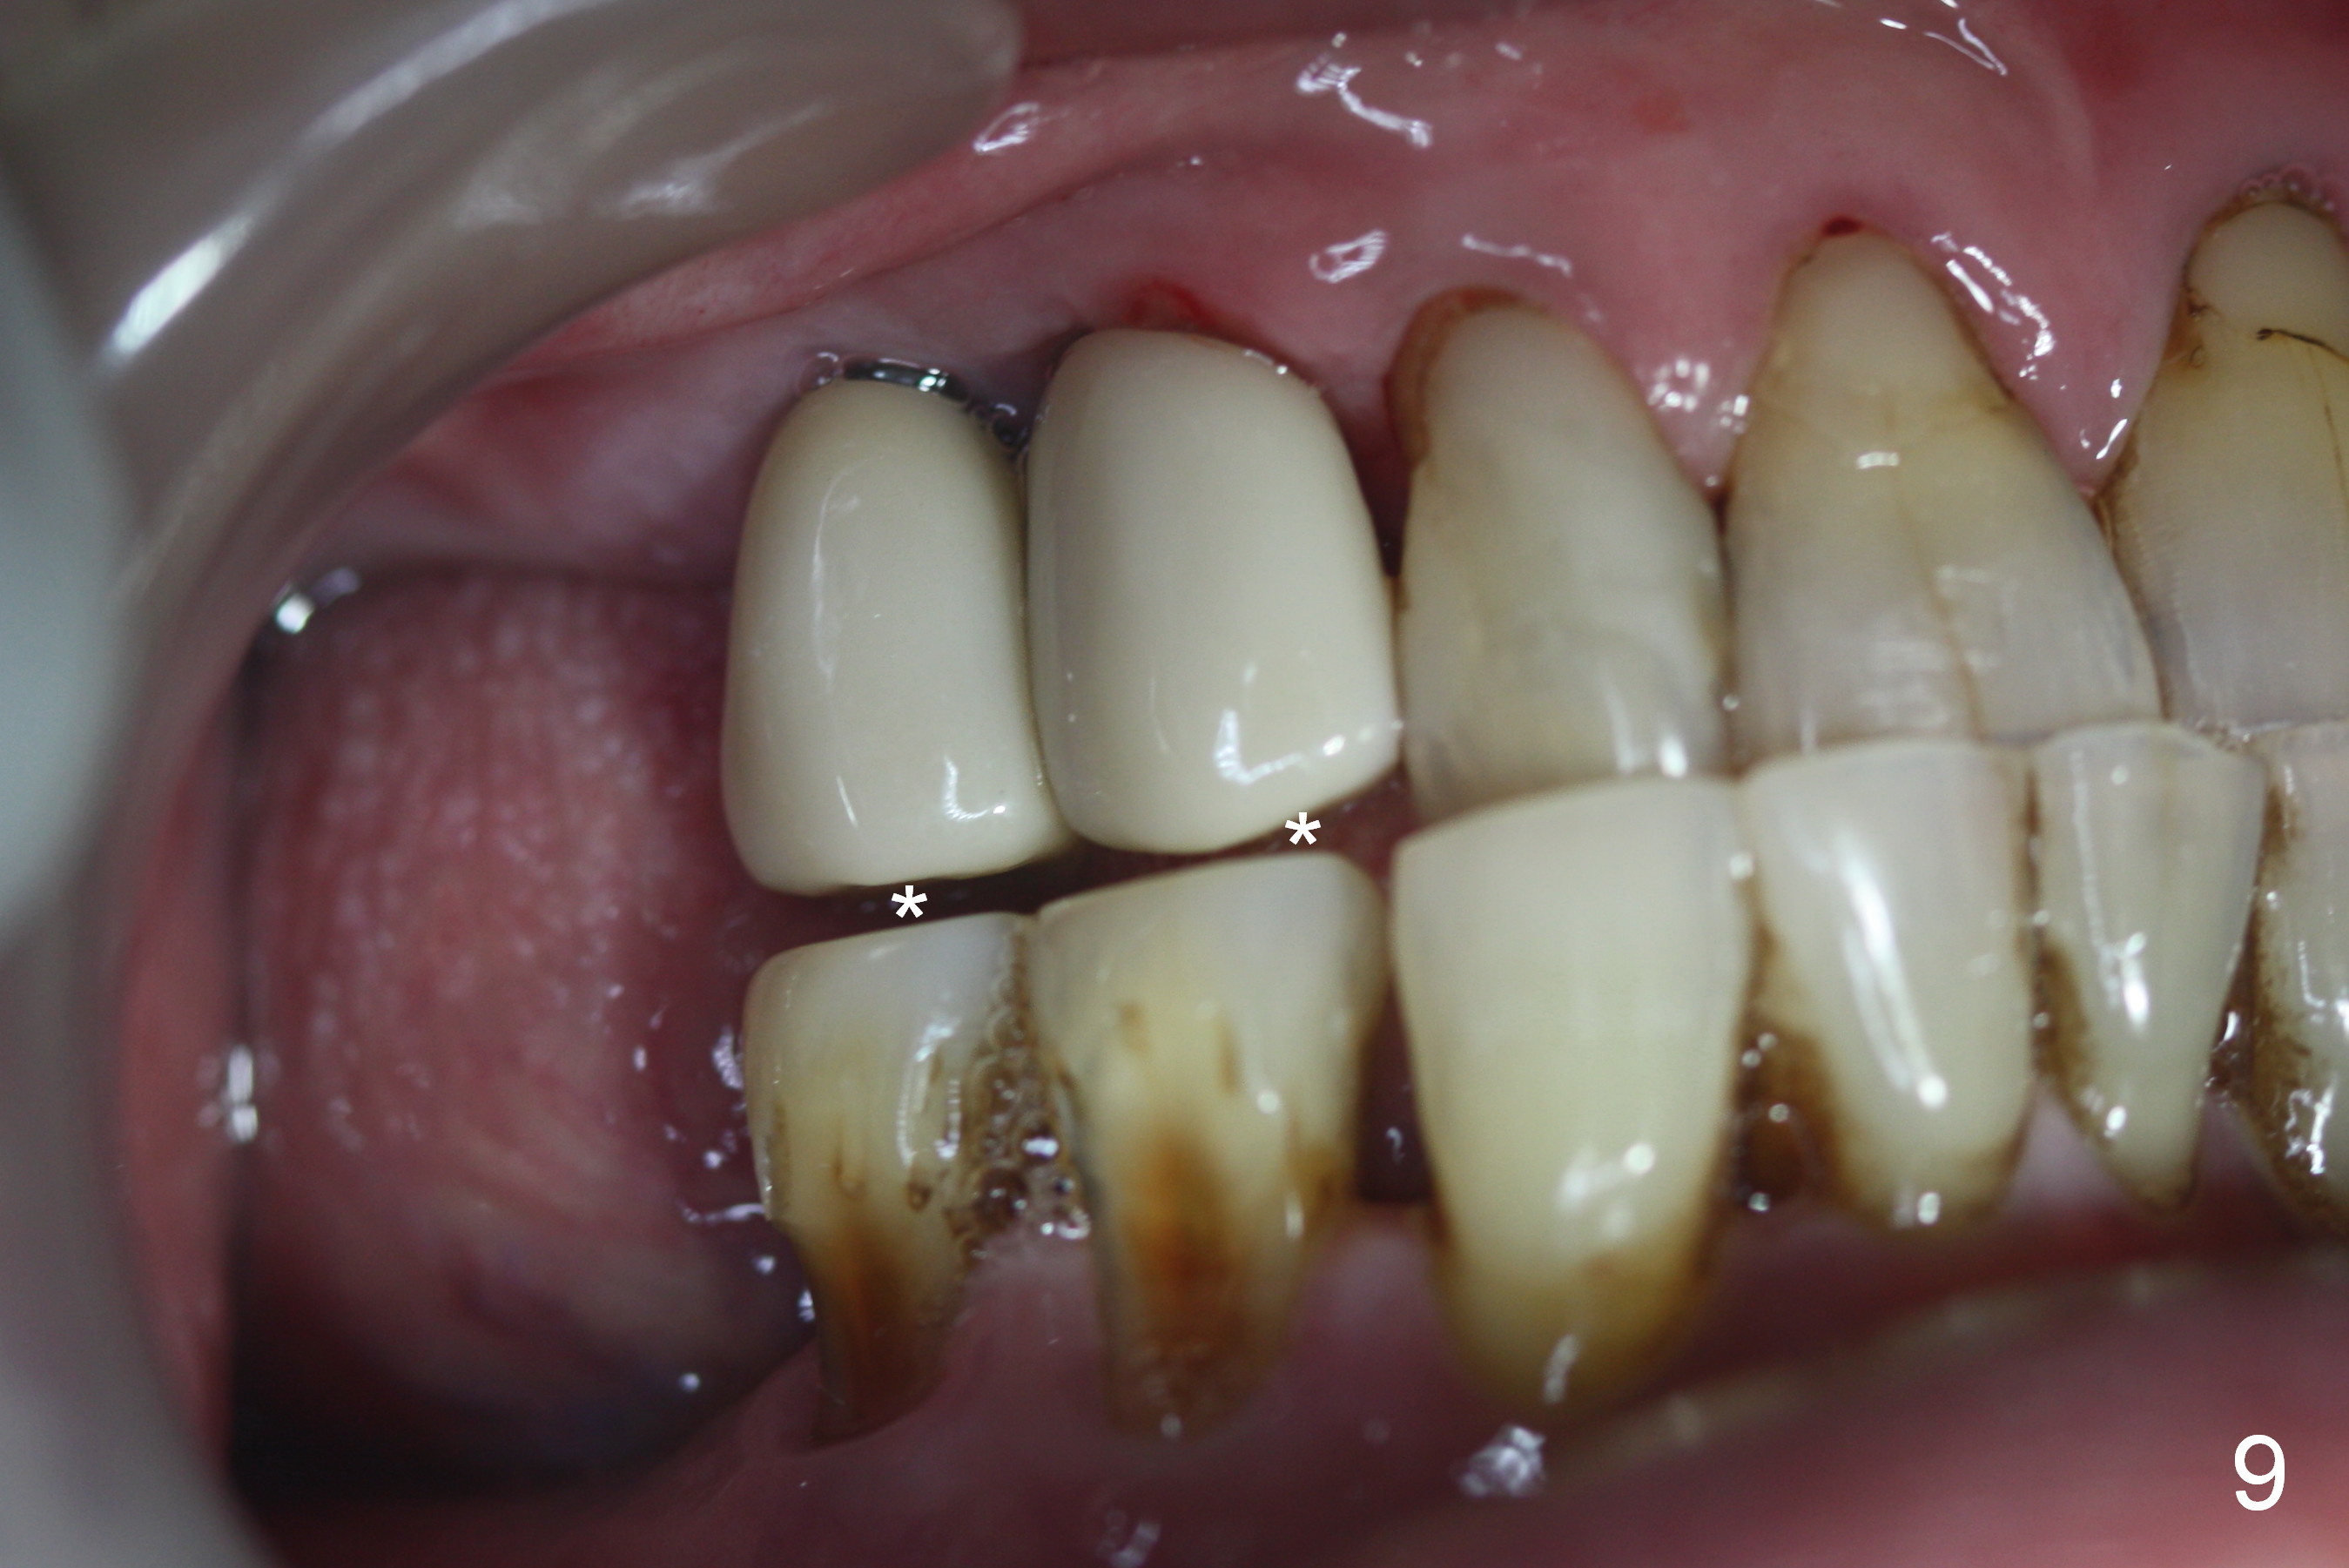

Bone density in the distal gap of #5 appears to have increased 3 months postop (Fig.7).  Prior to definitive restoration cementation (3.5 months postop), the buccal plate does not collapse (Fig.8).  There is no occlusal contact of the new restorations (Fig.9 *), probably due to bite discrepancy (Fig.10,11).